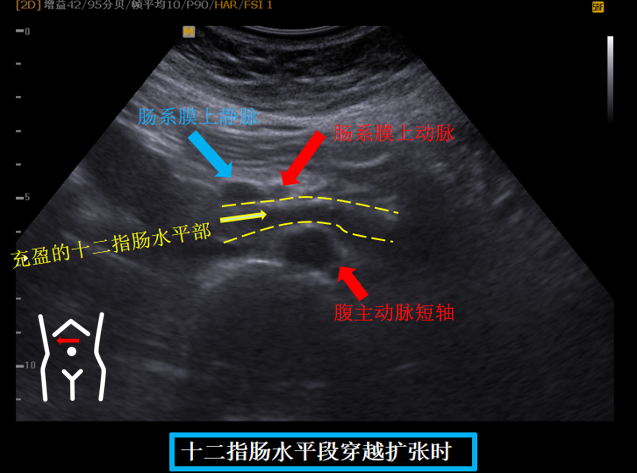

第五组切面

十二指肠水平段穿越肠系膜上动脉上静脉与腹主动脉间隙切面。